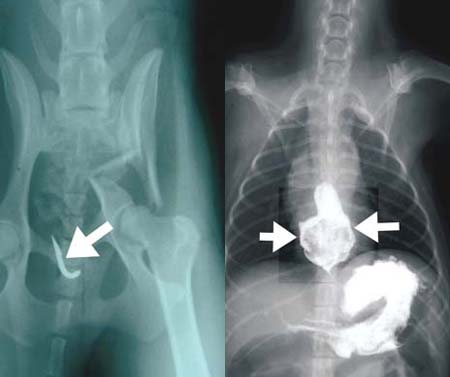

A: อันดับแรกคงอยู่ที่การซักถามและสอบประวัติ รวมถึงคำยืนยันของเจ้าของซึ่งเปรียบเหมือนเป็นพยานปากเอกที่สำคัญ จากนั้นเป็นการตรวจร่างกาย โดยการเปิดปากสำรวจในช่องปาก หรือคอส่วนต้น หรือกระทั่งการคลำตรวจในช่องท้องก็สามารถเป็นอีกวิธีในการตรวจหาได้เช่นกัน จากนั้นถ้ามีข้อสงสัยต่อเนื่องก็คงต้องอาศัยวิธีทางรังสีวิทยา หรือทางการใช้เครื่องอัลตร้าซาวด์ช่วยวินิจฉัยต่อเนื่องได้ โดยหากสิ่งแปลกปลอมเป็นกระดูก ก้อนหิน หรือสิ่งของที่มีส่วนประกอบเป็นโลหะ ก็จะง่ายต่อการมองเห็นจากภาพถ่ายทางรังสีวิทยา แต่ถ้าเป็นเศษพลาสติก เศษผ้า เศษด้าย ไม้ เมล็ดมะม่วง เมล็ดทุเรียน ก็อาจมีความจำเป็นจะต้องนำเทคนิคพิเศษทางรังสีวิทยามาช่วย เช่น การให้สัตว์กลืนสารทึบรังสี หรือที่เราเรียกว่ากลืนแป้งเข้าไป เพื่อช่วยให้แป้งเข้าไปเคลือบสิ่งแปลกปลอมเหล่านั้น ทำให้เรามองเห็นได้ง่ายขึ้นได้จากภาพถ่ายรังสี รวมทั้งถ้ามีการอุดตันก็จะพบได้ว่าแป้งที่กลืนนั้นจะสะสมอยู่บริเวณส่วนหน้าที่มีการอุดตันได้อย่างชัดเจน แต่ถ้าโชคร้ายในกรณีที่มีการทะลุเข้าช่องท้อง ก็จะพบว่ามีสารทึบรังสีแพร่กระจายออกมาจากทางเดินอาหารได้อย่างชัดเจน แต่ถ้าในบางโรงพยาบาลสัตว์ที่มีเครื่องอัลตร้าซาวด์ ก็สามารถใช้อุปกรณ์นี้ในการช่วยวินิจฉัยได้ โดยการสแกนดูความผิดปกติภายในบริเวณทางเดินอาหารที่สงสัยว่ามีการอุดตันเกิดขึ้นหลังจากวินิจฉัยจากภาพถ่ายทางรังสีแล้ว